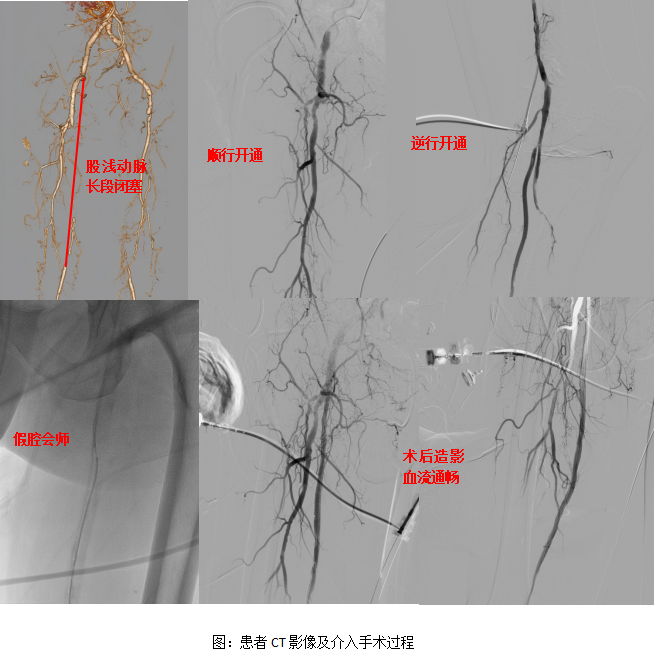

今日房县网讯 通讯员 张正宇 报道: 近日,十堰市人民医院介入科、内分泌科团队为一位74岁高龄的糖尿病足患者,成功实施了下肢动脉长段闭塞介入开通术。面对术中顺行、逆行路径均无法进入真腔的困境,团队凭借创新的“假腔会师”技术攻克难关,最终为患者打通了闭塞的血管,保住了濒临坏死的患肢。

入院检查发现,导致创面无法愈合的根本原因,是其右侧股动脉存在长达300毫米的完全闭塞,血供无法抵达足部,这是典型的糖尿病合并下肢动脉硬化闭塞症。若不及时开通血管,患者极有可能面临足部坏疽甚至截肢的风险。

面对这一棘手病例,十堰市人民医院介入科团队迅速制定了详细的手术方案。然而,手术的复杂程度远超预期:常规的顺行路径开通时,导丝导管进入血管假腔后反复尝试均无法回到真腔;随后,团队尝试从腘动脉逆行开通,但同样在假腔内“迷路”,无法进入真腔。

“绝不能放弃!”主刀医生、十堰市人民医院介入科主任谢兴武果断决定改变思路。团队调整策略,在张正宇医师的配合下,谢兴武主任利用导丝导管在假腔内的空间,采用顺行与逆行双向同步操作的方式,在血管假腔内精准定位,最终实现了“假腔会师”,成功建立了通过闭塞段的工作通道。

随后,团队顺利植入支架,血管瞬间恢复通畅。原本苍白冰冷的足部立刻变得红润温暖,足背动脉搏动也恢复了有力的跳动。